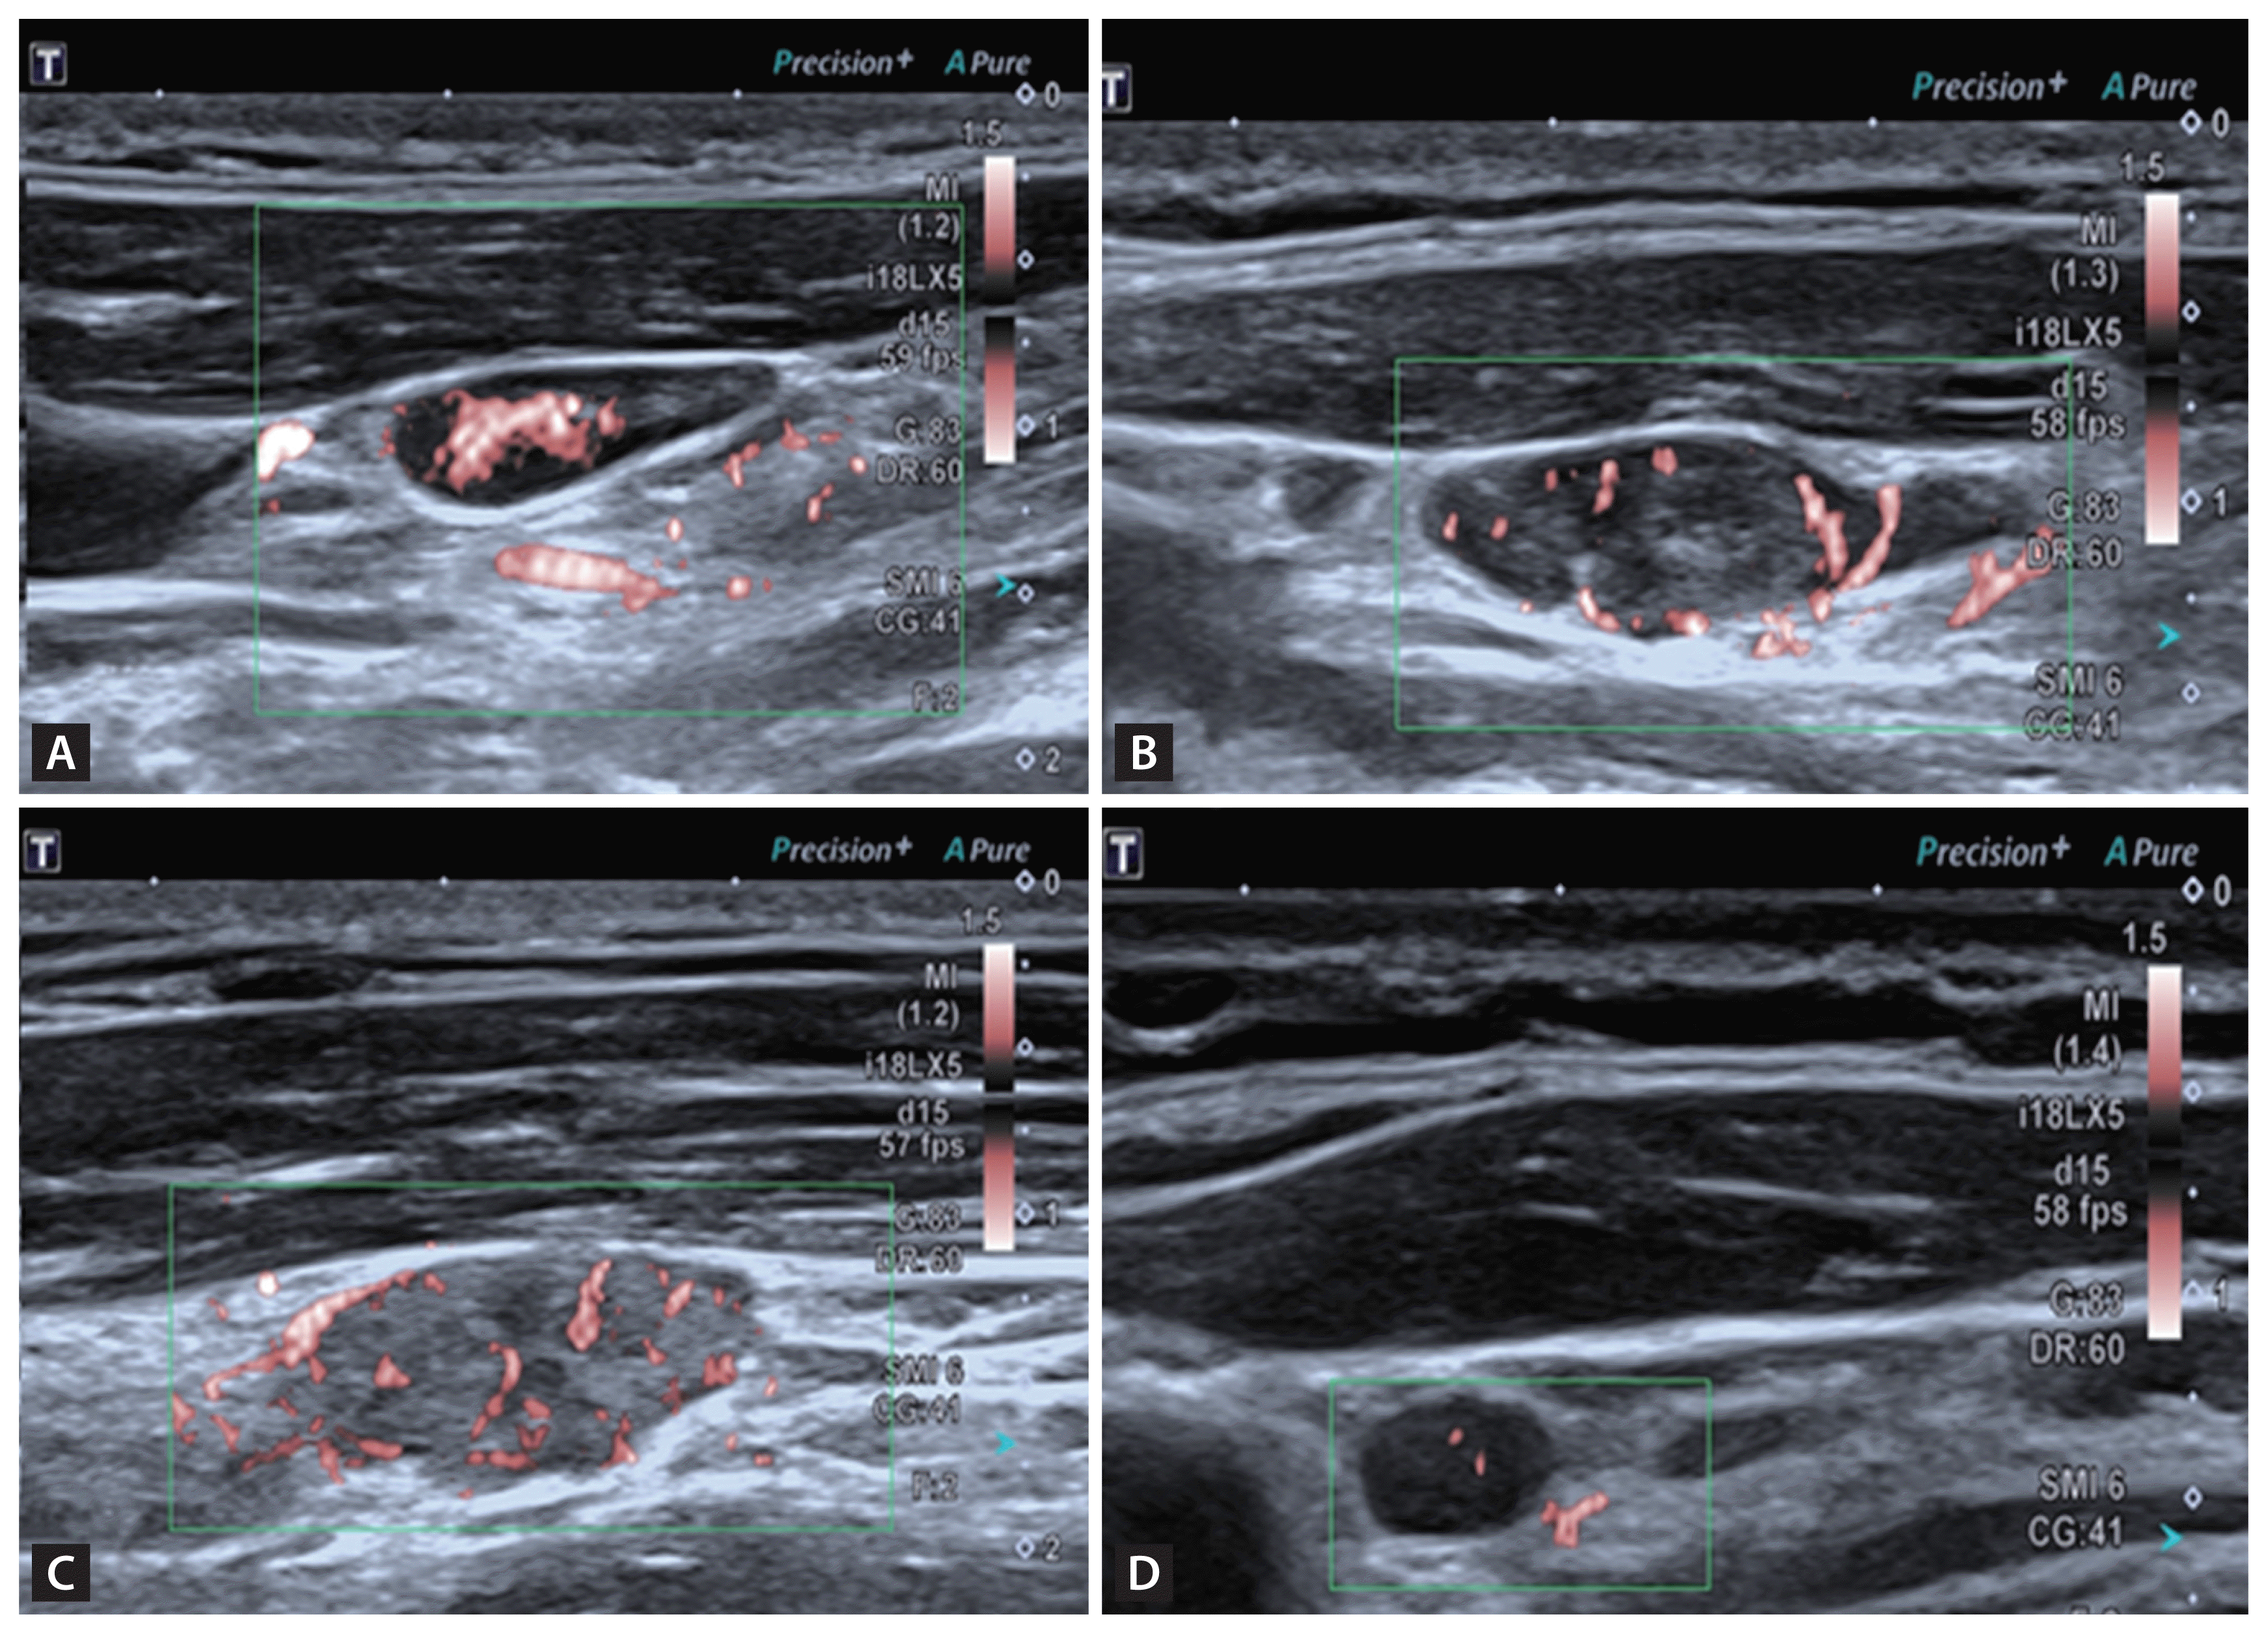

After that, SMI and SWE were performed with minimum pressure from the transducer. The mean value of the vascular index (VI) and SWE for each lymph node was calculated from three measurements of each node obtained from longitudinal views. The parameters of SMI were shown as follows: velocity scale was 1.5 cm/s. For qualitative analysis, vascular pattern of lymph node was observed and reported. For quantitative analysis, VI was measured at the image with the strongest blood signal. VI is the ratio of number of pixels of vascular signal to the whole lymph node (tracing the outline of lymph node) and was automatically calculated and displayed on the screen (Fig. 1A). Margin of each lymph node was manually traced and the outline was on behalf of region of interest (ROI). We then switched to SWE mode and stiffness of lymph node was measured. Shear waves generated from the probe and displayed in a real-time color map. The average stiffness of lymph node (SWEmean) was assessed by placing ROI (tracing the outline of lymph node) and was expressed in kPa (Fig. 1B).

Examples of measurement using SMI and SWE. Margin of each lymph node were manually traced and the outline was on behalf of ROI. (A) VI was the ratio of number of pixels of vascular signal to the whole lymph node (tracing the outline of lymph node) and was automatically calculated and displayed at the bottom. (B) Average elasticity (kPa) of ROI was displayed automatically. SMI, superb microvascular imaging; SWE, shear wave elastography; ROI, region of interest; VI, vascular index.